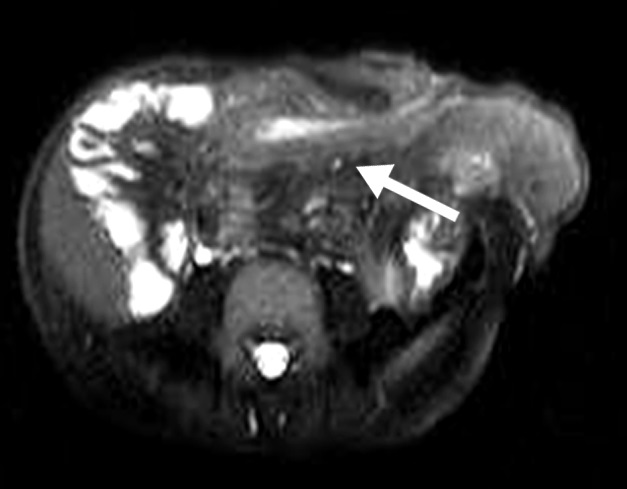

Figura 4

Paciente con enfermedad de Crohn de 10 años de evolución, cursando gestación de 13 semanas. Secuencia eco de gradiente coronal. Asas delgadas de paredes engrosadas en la fosa ilíaca derecha, se idenjpgican los vasos rectos ingurgitados como estructuras lineales perpendiculares a la pared constituyendo el signo del peine (flecha).